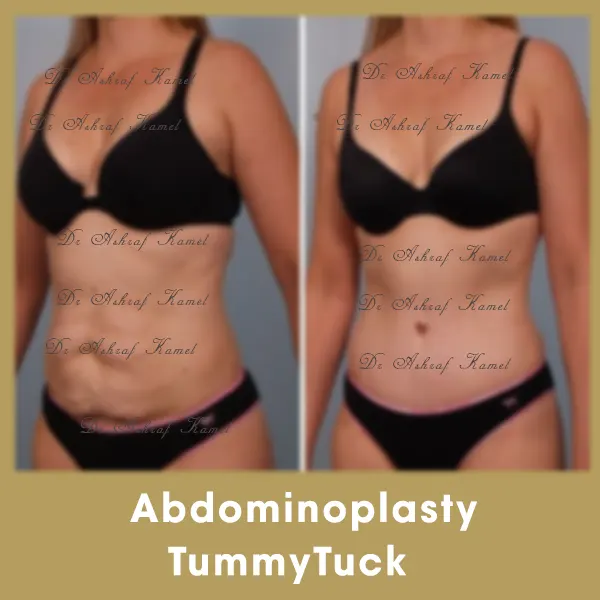

صور حالات مرضى

اشتهر بتقديم احدث تقنيات طب التجميل والجراحات التجميلية وعمليات تنسيق القوام، تكبير وتصغير وشد الثدي وتجميل الأنف وعلاج الترهلات، شد الذراعين و ازالة الترهلات، رفع الأرداف و علاج جراحات السمنة ونحت العضلات والـ6 باكس عالي التحديد، شفط الدهون بالفيزر والجي بلازما واحدث التقنيات بالخريطة الالكترونية، تجميل الجفون، تجميل الاذن وعلاج الاذن الوطواطية.